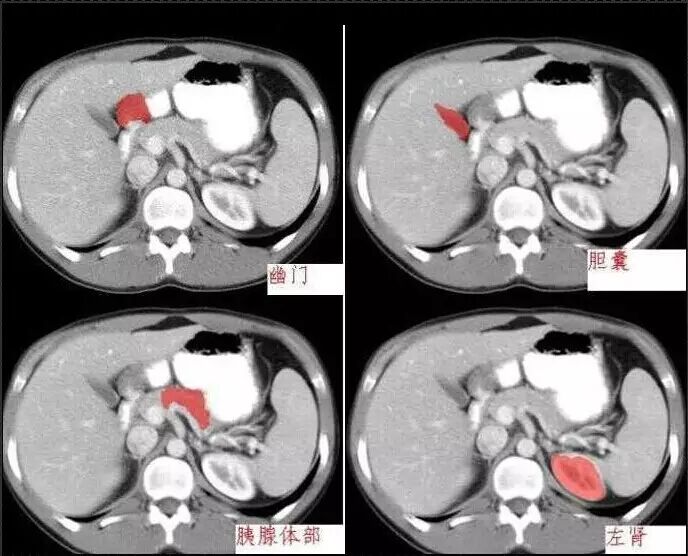

十分钟学会腹部CT解剖(多图)